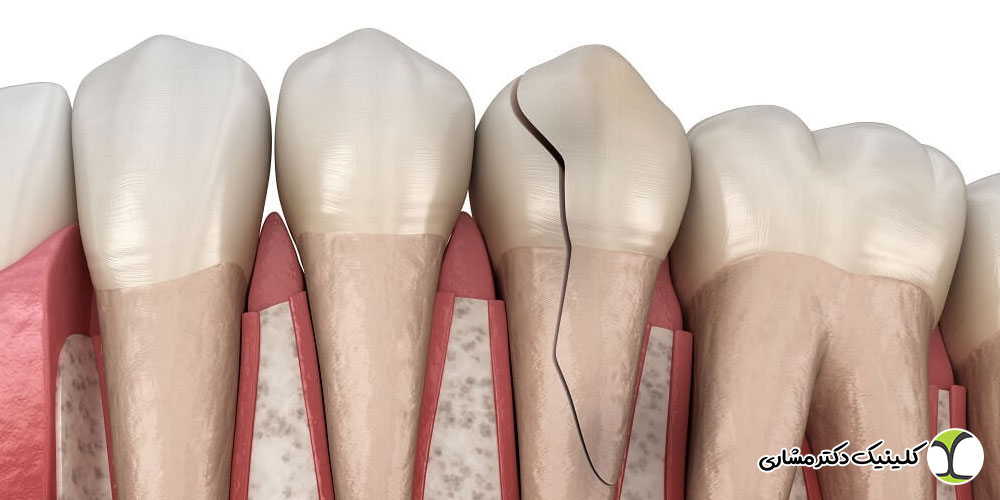

چرا دندان عقل روی عصب خطرناک است؟

دندان عقل درگیر با عصب در بیش از ۹۰٪ موارد، در بلندمدت میتواند باعث تشکیل کیست، ضایعه یا تخریب استخوان فک شود. این ضایعات ممکن است:

- استخوان وسیعی را تخریب کنند

- به عصب فشار وارد کنند

- سایر دندانهای فک پایین را تحت تأثیر قرار دهند

- درمان را پیچیدهتر و پرهزینهتر کنند

در مواردی که بیمار بدون علامت است، خطر حتی بیشتر است؛ زیرا ضایعه میتواند سالها رشد کند بدون اینکه بیمار متوجه شود.